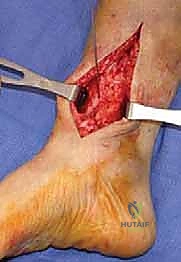

2. الشق الجراحي والوصول الآمن

يُجري الدكتور هطيف شقاً جراحياً دقيقاً في الجزء السفلي من الساق. بفضل خبرته في الجراحة الميكروسكوبية والتشريح الدقيق، يتم إبعاد الأوتار، والأوعية الدموية، والأعصاب الحساسة بعناية فائقة لحمايتها من أي ضرر.

5. التثبيت الصلب وزراعة الطعم العظمي

في حالة "فتح الإسفين"، يتم وضع طعم عظمي (يؤخذ غالباً من عظم الحوض للمريض أو طعم صناعي متقدم) لملء الفراغ. بعد ذلك، يقوم الدكتور هطيف بتثبيت العظم في وضعه الجديد القويم باستخدام شرائح معدنية تشريحية مصممة خصيصاً لهذه المنطقة (Anatomical Locking Plates) ومسامير قوية. هذا التثبيت الصلب يضمن التئام العظم بشكل صحيح.